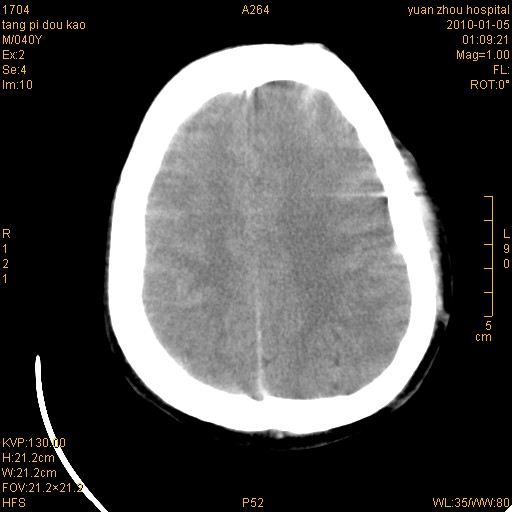

1)左侧颞枕部硬膜外血肿。2)右侧额部硬膜下血肿。3)双侧额叶及右侧基底节下部脑挫裂伤。4)蛛网膜下腔出血。5)脑水肿。6)左侧前组筛窦及左侧额窦炎症。

前纵裂池的出血是硬膜下还是蛛网膜下腔?右额叶深区血肿还是基底节血肿?